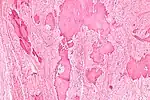

| Low magnification micrograph of a calcified ovarian fibroma in the context of nevoid basal cell carcinoma syndrome. H&E stain. | |

On gross pathology, they are firm and white or tan. On microscopic examination, there are intersecting bundles of spindle cells producing collagen.

There may be thecomatous areas (fibrothecoma). The presence of an ovarian fibroma can cause ovarian torsion in some cases.

Diagnosis is usually made by ultrasonography showing a solid ovarian lesion, or, on some occasions, mixed tumors with solid and cystic components.[1] Computed tomography and magnetic resonance imaging can also be used to diagnose fibromas. In a series of 16 patients, 5 (28%) showed elevated levels of CA-125.[1] Histopathology demonstrates spindle-shaped fibroblastic cells and abundant collagen.[3]